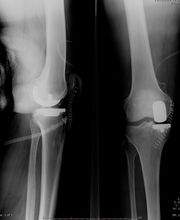

Il Dr. Grillo Pier Paolo, laureato con lode in Medicina e Chirurgia, è specializzato in Ortopedia, Traumatologia e Fisioterapia. Dal 1980 lavora presso il CTO di Torino, ove attualmente presta servizio presso la Clinica Ortopedica Traumatologica Universitaria in qualità di Dirigente Ortopedico - Traumatologo di I° Livello, che svolge la sua attività di sala operatoria, ambulatori specialistici e pronto soccorso. Si occupa prevalentemente di chirurgia del ginocchio e dell'anca con riferimento: Chirurgia protesica(totale, parziale, revisioni e reimpianti, trattamento delle complicanze settiche), Chirurgia artroscopica (ricostruzioni legamentose LCA-LCP, meniscectomie selettive, suture meniscali, trattamento dei danni cartilaginei),chirurgia della patologia rotulea (riallineamenti prossimale e distale,trattamento della lussazione recidivante,condroplastica, ricostruzione legamento patello-femorale) chirurgia delle deformità (ginocchio varo o valgo), traumatologia, patologie degenerative post-traumatiche. Ha partecipato a numerosi congressi, convegni e corsi di aggiornamento in Italia e all'estero; ha partecipato a numerosi Cadaver Lab all'estero in qualità di Tutor; è coautore di numerose pubblicazioni scientifiche edite a stampa. Per contatti e prenotazioni: studio medico: Studio Medico Crocetta - c.so Galileo Ferraris 107, Torino tel.: 011-5818892. Per ulteriori informazioni visitate il sito: www.studiocrocetta.it.